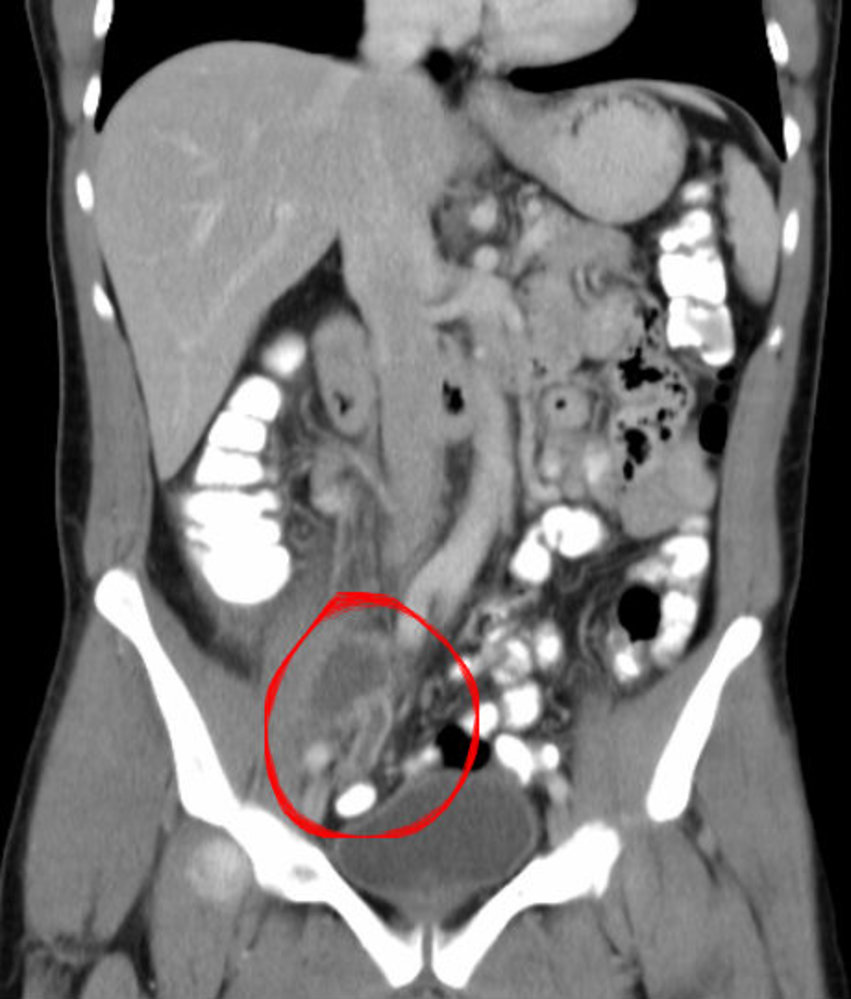

CT abdomen with IV contrast

CT abdomen is the most accurate initial imaging modality for appendicitis. [12][29]

Supportive findings [29]

- Distended appendix (diameter > 6 mm)

- Edematous appendix with periappendiceal fat stranding

- Possible appendiceal fecalith: focal hyperdensity within the appendiceal lumen

- Evidence of complications

- Consider low-dose CT scan (with IV contrast) to minimize radiation exposure. [33][34]

- Consider CT without contrast in patients with contrast allergy. [34]

Adding oral and/or rectal contrast does not improve diagnostic accuracy and may delay diagnosis. [10]